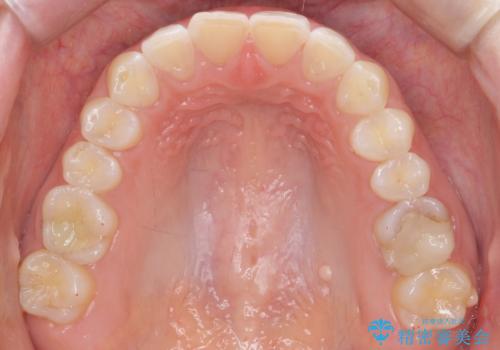

- 下の前歯のがたつきを治したいとのことでした。

上の前歯のちょっとしたねじれも治療しています。

軽度だったため、部分矯正のコースで短期間で治療しました。

下の歯並びを並べるため、わずかに歯を削合しています。

そうしないと、前に出て上の前歯に強く当たってしまうためです。また、後戻りを防ぐ効果もあります。